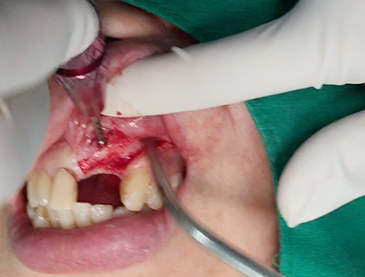

Horizontal ridge augmentation

Vertical ridge augmentation

Simultaenous bone grafting for implants

Partial edentulous clinical cases

Implants/Bone Grafting